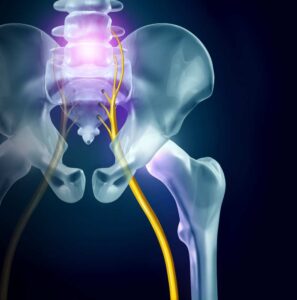

What Causes Neck Spasms?

When a muscle spasm occurs, your muscles tighten and then contract involuntarily. This can happen suddenly and without warning. Muscle spasms can occur all over the body, and the location of your muscle spasms can help determine the root cause. You can’t control when muscle spasms occur, and they can…